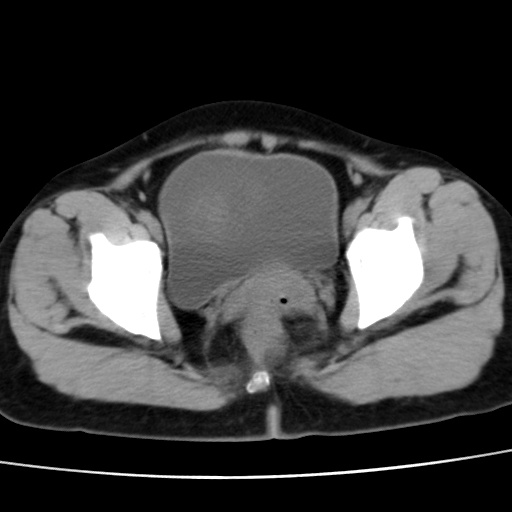

子宫多发肌瘤吗

多发性子宫肌瘤.

考虑多发子宫肌瘤,子宫直肠窝双囊性占位,另直肠周围脂肪密度增高,不知有何病史

支持考虑多发子宫肌瘤~!子宫直肠陷凹积液?

支持考虑多发子宫肌瘤~!子宫直肠陷凹积液!

子宫肌瘤,宫体部后方见液性密度影,是肠道还是子宫与直肠陷窝积液不好说,我觉得它的位置有点高

支持考虑多发子宫肌瘤!子宫直肠陷凹积液!

患者发热,而子宫直肠窝液性灶有明显边缘且局限且囊性,不除外为包裹性积液或脓肿

支持考虑多发子宫肌瘤,子宫直肠陷凹积液可能。

考虑多发子宫肌瘤

1)考虑子宫肌瘤可能性大。2)子宫后方囊性占位性病变,不排除卵巢囊肿可能。

考虑多发子宫肌瘤。子宫后方囊性占位性病变,不排除卵巢囊肿可能。